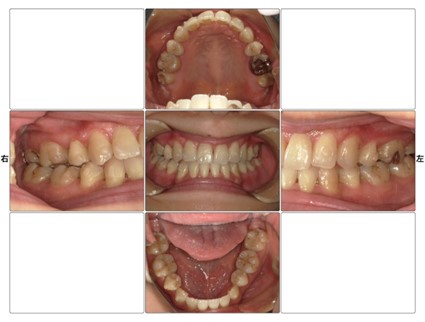

※歯についている凹凸がアタッチメントです

アタッチメントとは、歯の表面に専用の樹脂(レジン)でつける小さな突起物のことです。形や大きさは治療計画によって異なりますが、一般的には米粒よりも小さく、歯の色に近い素材が使われるため、ほとんど目立ちません。